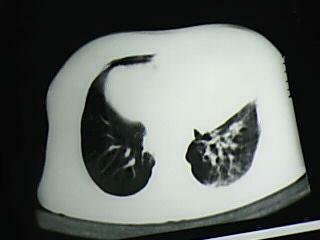

以下是引用bmw011在2009-4-14 19:14:00的发言:[br]右肺继发型肺结核---纵隔淋巴结多发钙化----左肺支扩。支持

以下是引用杀毒软件在2009-4-14 17:52:00的发言:[br]考虑---右肺继发型肺结核---纵隔淋巴结多发钙化----左肺支扩

以下是引用黑白光影在2009-4-14 20:36:00的发言:[br]右肺继发型肺结核;左下慢性支气管炎性病变。